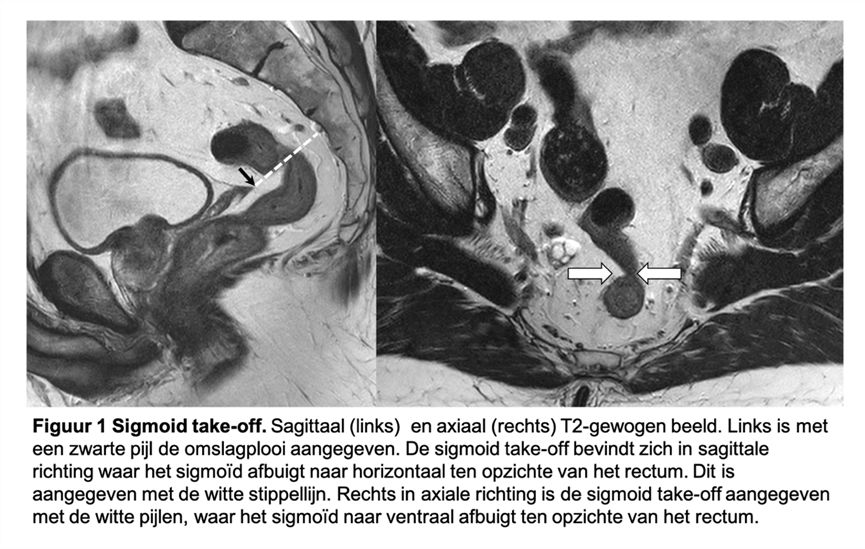

Voor eenduidigheid in interpretatie van de richtlijn, dagelijkse praktijkvoering, kwaliteitsregistratie en wetenschappelijk onderzoek is het van belang een gestandaardiseerde definitie te hebben van het rectum. Vervolgens kan op basis van deze definitie worden bepaald wat beschouwd wordt als een rectumcarcinoom. In het verleden werd vaak de afstand van de onderrand tot de anus gehanteerd op basis van endoscopie (tot 15 cm), maar dit is onbetrouwbaar en respecteert ook niet de anatomische variatie tussen patiënten. In analogie aan de klinische TNM-stadiëring was er binnen de groep van experts consensus dat beeldvorming ook voor de definitie van het rectum de modaliteit van voorkeur is. Uiteindelijk werd consensus verkregen over de zogenaamde ‘sigmoid take-off’ op MRI of CT om het onderscheid tussen colon en rectum te maken (D’Souza, 2019). Binnen deze consensus meeting werd geen uitspraak gedaan hoe dit vertaald moet worden naar de definitie van een rectumcarcinoom. De werkgroep heeft een rectumcarcinoom gedefinieerd als een tumor waarvan de onderrand distaal van of op het niveau van de ‘sigmoid take-off’ ligt. Figuur 1 toont hoe de sigmoid take-off kan worden bepaald. Bij het identificeren van de sigmoid take-off wordt gebruik van de bocht die het rectum maakt naar ventraal op de sagittale en axiale serie. Echter, bij suboptimale scanhoek, anatomische variaties (bijv. enterocele, retroflexie van de uterus of descensus perinei) is de sigmoid take-off op deze manier niet altijd goed te zien. In deze gevallen is de peritoneale omslagplooi een behulpzaam anterieur landmark van de sigmoid take-off.

Figuur 1. Sigmoid take-off

Een internationale, expert-based Delphi consensus is bereikt over de definitie van het rectum (D’Souza, 2019). Op CT of MRI wordt het rectum gedefinieerd vanaf de anorectale overgang tot aan de sigmoid takeoff. Deze kan worden geïdentificeerd op axiale en sagittale opnamen. Axiaal is de ventrale projectie van het sigmoïd, daar waar het bovenste mesorectum vasthangt aan het sacrum bij de rectosacrale/prefasciale fascie, de transitie naar het mesocolon. Sagittaal kan deze projectie worden geïdentificeerd als de horizontale knik in het colon (zie figuur 1 in de overwegingen).